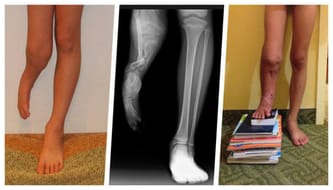

My son Alan has a rare and complicated leg deformity that he needs a third surgery at The Paley Institute in the US. Two previous surgeries took place there as well. The Polish healthcare system funded them. This time there is no chance for this to happen...

We have been fighting for Alan for the last 16 years. “The child has one shorter leg, but we are not sure what kind of defect is this, but it's only a leg. You should be happy that this isn't another severe disease, which could happen to your son" - this is what I heard straight after giving birth to my son. I wasn't ready for this, especially that all tests during pregnancy were fine.

Dr Dror Paley from the Paley Institute in Florida explained that Alan’s case happens once in a million births. But, most importantly, he knew how to treat such a defect. Finally we were given a chance, we were given hope, that modern medicine will save our boy’s leg.

We have taken him to the United States twice already and both surgeries were funded by Polish health care. Dr Paley has lengthened Alan’s tibial bone by 16 cm; he improved the functionality of the knee and ankle, as well as moved the tibia bone back to where it should be. The second trip to the USA would not have been possible without the support of donors (opens a new tab) who helped us to pay for a multi-month stay across the ocean.

Since then, Alan’s leg, which he wouldn’t have had by now without our determination, has been growing with him. It is almost an “adult” leg, but it is still 20cm shorter than his healthy leg. Dr Paley, is the only doctor who gave us hope for a full recovery that Alan will one day will have two equal legs.